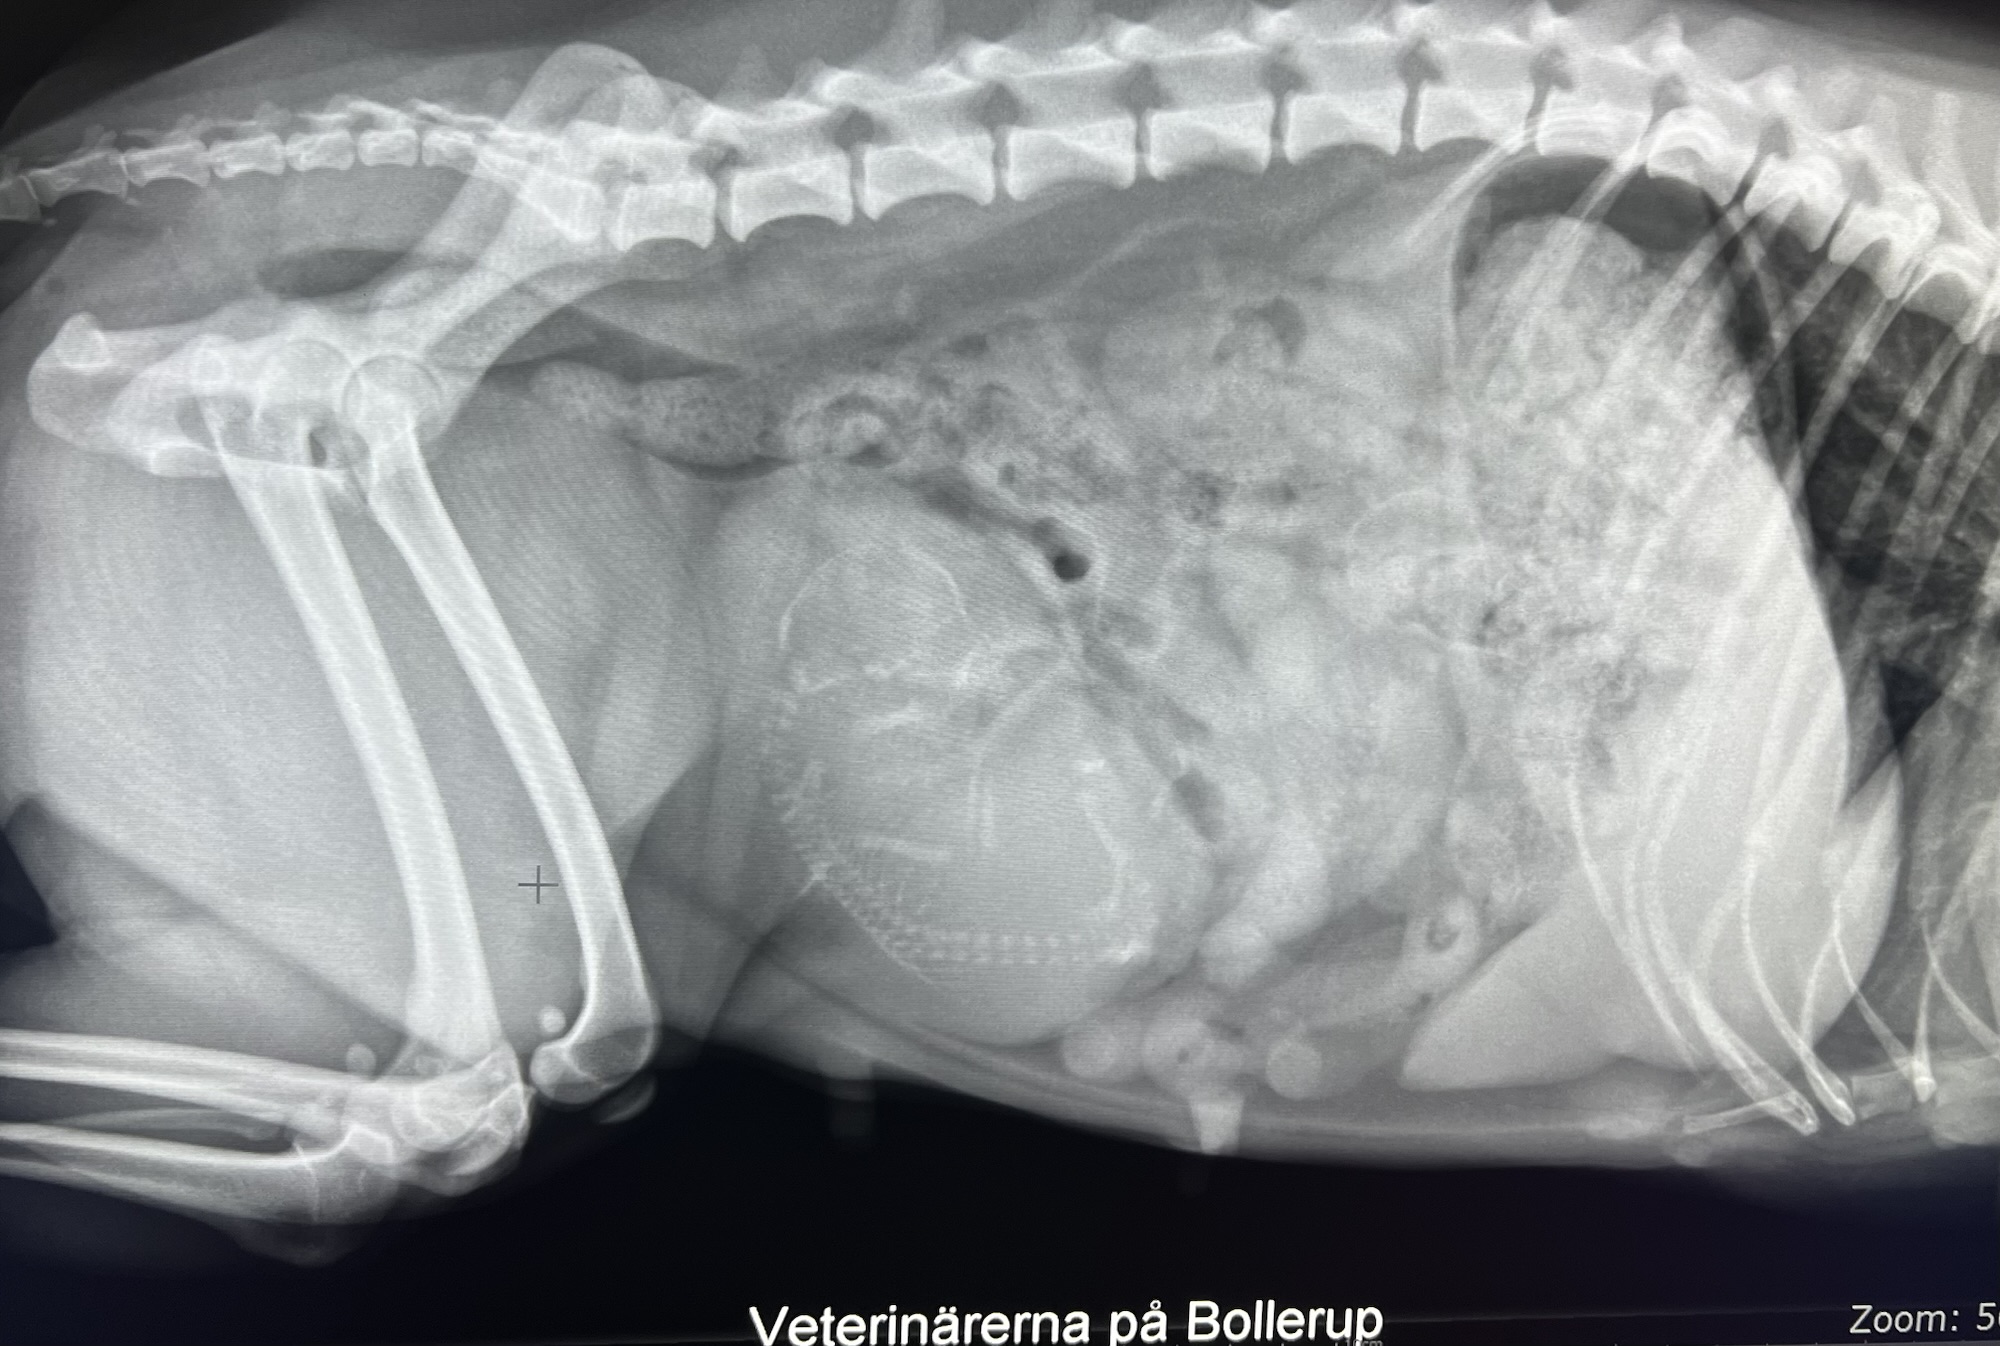

I skånsk snökaos i Januari var vi iväg och parade vår Ixia med fina Flinkagårdens Alfred. Men denna gången gick det inte vår väg, i tisdags när Ixia gått någon dag över tiden var vi nere hos Veterinärerna på Bollerup för att göra ett ultraljud för att se så att valparna mådde bra. Tyvärr så fanns där ingen hjärtaktivitet. Så igår genomgick Ixia ett kjejsarsnitt där man plockade ut två valpar, en tik och en hane, Stor och Liten. Nu är det vår prioritet att se till att Ixia läker och återhämtar sig. Dock så är vi så ledsna för de två familjerna som såg framemot att få välkomna varsin valp till sommaren. Vi vill än en gång rikta ett stort tack till personalen på Veterinärerna på Bollerup för otroligt fint bemötande och omhändertagande. Det är så viktigt att vi ser till att vårda våra lokala veterinärer och att vi värdesätter att de finns där för oss när vi behöver dom. Nu ska vi försöka ta in vad vi har varit med om och se framemot en fin sommar och sen får vi se vad tiden har framömför oss! Ta han om er och krama era hundar lite extra. 20260319